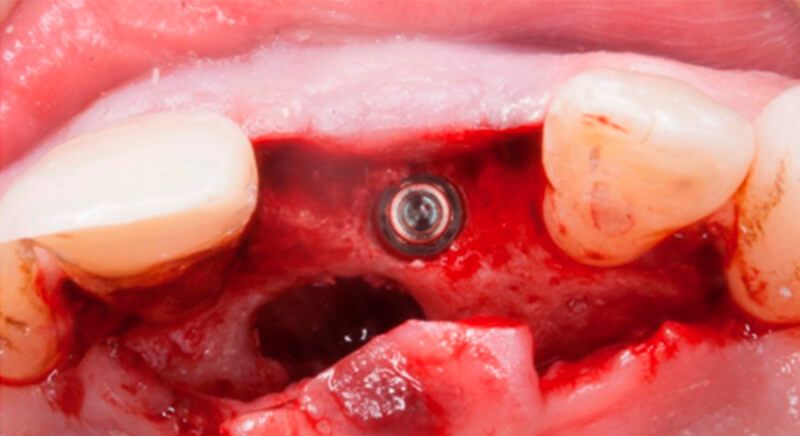

The guided surgery was performed by lifting a full thickness mucoperiosteal flap. A Biomimetic Ocean CC implant, diameter 3.5mm and length 10mm, was inserted using the surgical guide in the ideal three-dimensional position and the defects were regenerated with xenograft and reabsorbable membrane, the nasopalatine duct on the palatine side and the area of dehiscence on the vestibular.

During the same surgical intervention, a short 3mm Avinent healing abutment was positioned and fully covered by the flap. Primary closure was completed and we waited 6 months for the bone graft to mature.